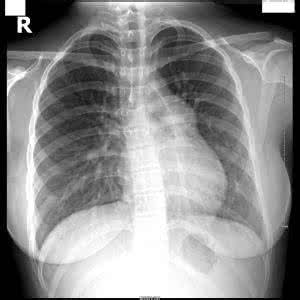

肺动脉高压是引起肺动脉压增高的原因,持续增加,超过正常值的肺动脉高压。临床表现为乏力、呼吸困难、晕厥、咯血等。肺动脉高压比年轻人多,是一种极为恶性的疾病,更是灾难性的,可以说这种疾病是癌症的心血管疾病。

肺动脉高压是在许多疾病过程中出现的病理过程。轻度的肺动脉高压不引起任何代谢和功能障碍,病人的症状和体征都是引起肺动脉高压的疾病的表现。严重的肺动脉高压本身可累积肺和心功能,从而间接影响全身。